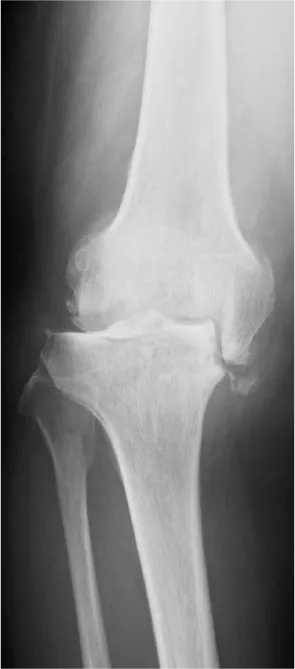

主な疾患

変形性膝関節症が最も多い疾患で、それに伴う半月板損傷やその他リウマチの患者さまが多くおられます。年代としては60代から80代までの方が一番多く、中には50代や90代の方で人工膝関節手術を受けられる方もおられます。

若いうちに人工膝関節を入れると、数十年後に入れ替えの手術を行う可能性も出てきますが、50代からの20年と70代からの20年ではやりたいことやできることも大きく変わってきますので、早く痛みをとってやりたいことをやる方がよいのではないでしょうか。

人工膝関節置換術

人工膝関節置換術は、傷んだ関節表面を切除し、金属やセラミック、ポリエチレンなどで作られた人工の関節に置き換える手術です。虫歯を削って被せ物をするような手術です。現在日本では年間9万件以上行われているといわれています。

• 高度破壊膝術前

• 術前計画

• 術後